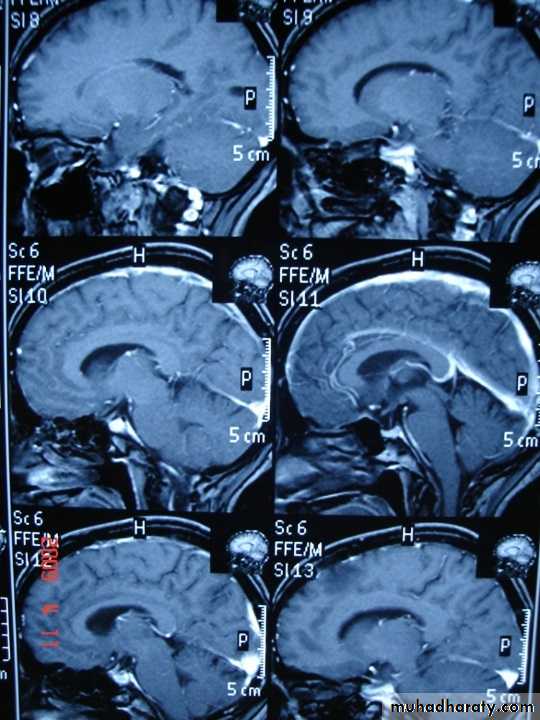

Coronal T1-weighted MRI image through a brain lesion showing homogeneity of the lesion, lack of a perceptible wall, lack of internal complexity, and CSF signal intensity. There is associated remodeling of the adjacent calvarium and brain displacement. These imaging features are typical of an arachnoid cyst.

Sagittal fluid-attenuated inversion recovery (FLAIR) weighted image through a brain lesion), showing homogeneity of the lesion, lack of a perceptible wall, lack of internal complexity, and CSF signal intensity. There is associated brain displacement. These imaging features are typical of an arachnoid cyst.

Axial T2-weighted MRI image through the midbrain, showing a right middle cranial fossa homogeneous lesion) with CSF signal intensity and no perceptible wall or internal complexity. There is associated remodeling of the adjacent sphenoid bone and brain displacement..